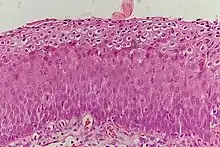

Normal cervical epithelium

Historically, abnormal changes of cervical epithelial cells were described as mild, moderate, or severe epithelial dysplasia. In 1988 the National Cancer Institute developed "The Bethesda System for Reporting Cervical/Vaginal Cytologic Diagnoses".[12] This system provides a uniform way to describe abnormal epithelial cells and determine specimen quality, thus providing clear guidance for clinical management. These abnormalities were classified as squamous or glandular and then further classified by the stage of dysplasia: atypical cells, mild, moderate, severe, and carcinoma.[13]

Depending on several factors and the location of the lesion, CIN can start in any of the three stages and can either progress or regress.[1] The grade of squamous intraepithelial lesion can vary.

CIN is classified in grades:[14]

Histology Grade Corresponding Cytology Description Image

CIN 1 (Grade I) Low-grade squamous intraepithelial lesion (LSIL)

• Mild epithelial dysplasia

• Confined to the basal 1/3 of the epithelium

• Typically corresponds to infection with HPV

• High rate of regression back to normal cells

• Usually managed expectantly

CIN 3 (Grade III)

• Severe dysplasia with undifferentiated neoplastic cells that span more than 2/3 of the epithelium

• May involve the full thickness

• May also be referred to as cervical carcinoma in situ

• CIN 3+ encompasses CIN 3, AIS, and cancer